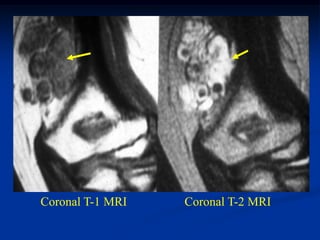

Case #1196.2 Ossifying Lipoma Cor T-1 Axial T-2 53 yr male with painless mass in knee for 3 yrs

• 116.